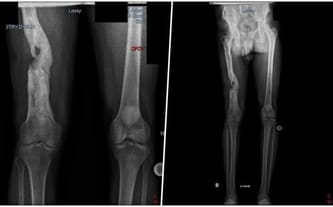

Kingsley 10 lat temu przeżył koszmar, od którego wszystko się zaczęło. Wracał do domu po służbie, w mundurze. Ktoś strzelił do niego od tyłu. Postrzał w prawe udo, strzaskana kość.

W Nigerii nie ma bezpłatnej służby zdrowia, więc rodzina do tej pory spłaca długi za operację...

Kingsley pracował ciężko w polskiej fabryce, by choć trochę spłacić długi. Niestety szybko los ponownie go pokarał. Niedługo po przylocie do Polski ciężko zachorował i niemal zmarł. Znaleziono go nieprzytomnego z bólu, z wysoką gorączką i spuchniętą jak bania nogą.

Lekarze byli zgodni: jedyny ratunk to operacja.

Niestety wszyscy odmawiali leczenia. Ze względu na ryzyko, nie chcieli się podjąć przeprowadzenia operacji. A stan zapalny wciąż się rozwijał. My jednak chcieliśmy uratować mu życie i udało się. Szpital w Otwocku przeprowadził dwie skomplikowane operacje, które zakończyły się sukcesem.